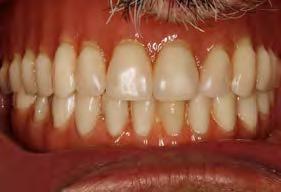

Figura 2 y 3. Figuras intraorales del paciente de 67 años que acude a la consulta para rehabilitación sobre implantes superior, portador de una prótesis completa removible con una atrofia ósea evidente al ser la prótesis retirada. Figura 4. La radiografía inicial muestra una atrofia marcada en sentido vertical, que debe ser constatada posteriormente mediante un TAC así como para la planificación de la colocación de los implantes. Figura 5 y 6. Encerado diagnóstico para comenzar la planificación de la colocación de los implantes superiores guiados por la posición ideal que deben tener los dientes en la prótesis. De este encerado se realiza una guía radiológica que nos permita trasladar estas posiciones al TAC de planificación.

Fueron reclutados 6 pacientes en los que se colocaron 30 implantes para realizar rehabilitaciones completas. La edad media de los pacientes incluidos en el estudio fue de 66.75 años (+/- 5,16) y un 86.7% fueron mujeres. El 63.3% de los implantes se insertaron en el maxilar superior y el 36.7% restante en la mandíbula, formando parte de 4 rehabilitaciones

completas superiores y 3 inferiores. Todos los implantes presentaron una longitud de 5.5 m m, con diámetros comprendidos entre los 2.5 y los 5.5 mm. Las posiciones de los implantes corresponden a distribuciones biomecánicas para la realización de prótesis completas tanto en el maxilar como mandíbula (incisivos, premolares y molares). Los diámetros y longitudes de los implantes incluidos en el estudio en función de

181. Septiembre 2023 51 Rehabilitaciones completas implantosoportadas

su posición se muestran en la Figura 1.

Figura 7­9. Cortes de planificación del cone beam donde observamos la extrema atrofia vertical y la posición en la que deberían situarse los dientes con una gran discrepancia entre esta posición y la base ósea. Vemos también como se planifican implantes extracortos de 5.5 mm de longitud en todas las localizaciones. Figura 10. Radiografía panorámica tras la colocación de los implantes.

En las Figuras 2­17 se puede observar uno de los casos incluidos en el estudio.